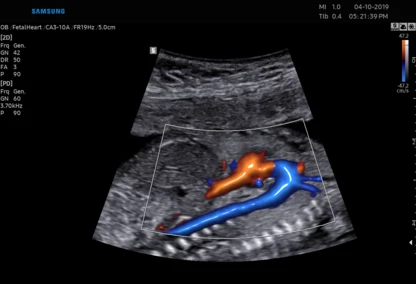

Diagnostykę obrazową przeprowadzamy z wykorzystaniem sprzętu Samsung HERA W9. To najnowszy aparat klasy premium – z kompletem głowic USG wysokiej rozdzielczości w tym głowicą USG 3D/4D. Doskonała jakość obrazu przekłada się na wiarygodność wyników.

Dostęp do nowoczesnej aparatury pozwala na obrazowanie przepływów w naczyniach krwionośnych. Dlatego wykonujemy również badania USG Doppler:

Ponadto jesteśmy w stanie zmierzyć przepływy w naczyniach u kobiet ciężarnych oraz płodu.